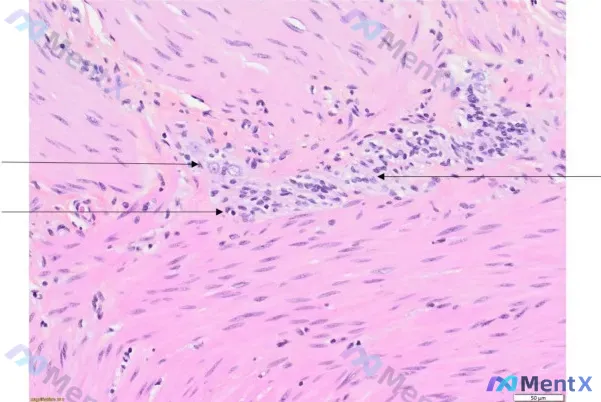

- H&E镜下:平滑肌背景中见巢状/条索状的圆形/多边形细胞,核偏圆、染色质细颗粒状、核仁可见、核浆比高,看起来有“异型性”;

- 关键细节:可见淋巴细胞与神经网、神经节细胞接触。

最初的形态学分析曾先往“上皮源性肿瘤浸润平滑肌”靠,但后来因为第二条细节,整个鉴别逻辑被推翻了。